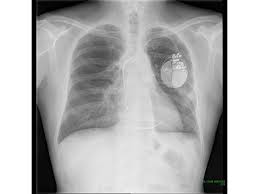

① 흉부 X선 촬영

기본적인 선별검사로 폐암 유무를 확인하지만, 초기 폐암은 놓칠 가능성이 있어 단독 사용은 한계가 있습니다.